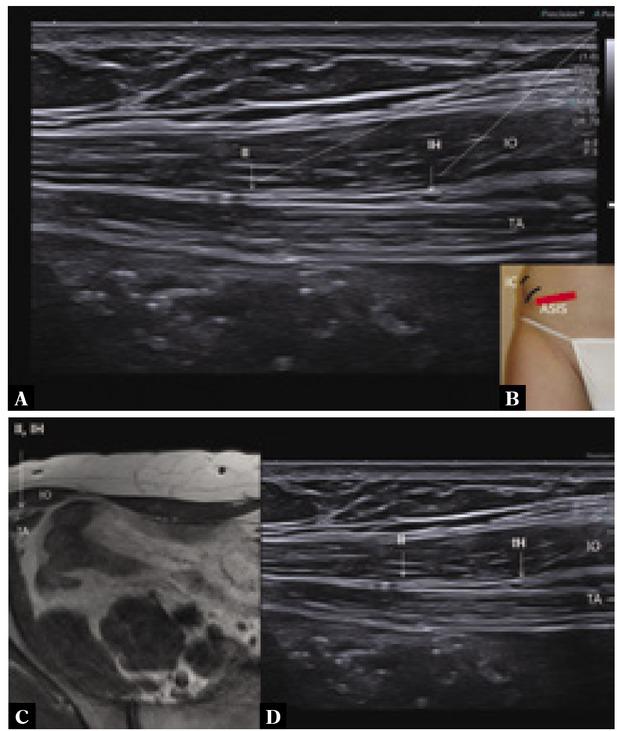

Fig. 1